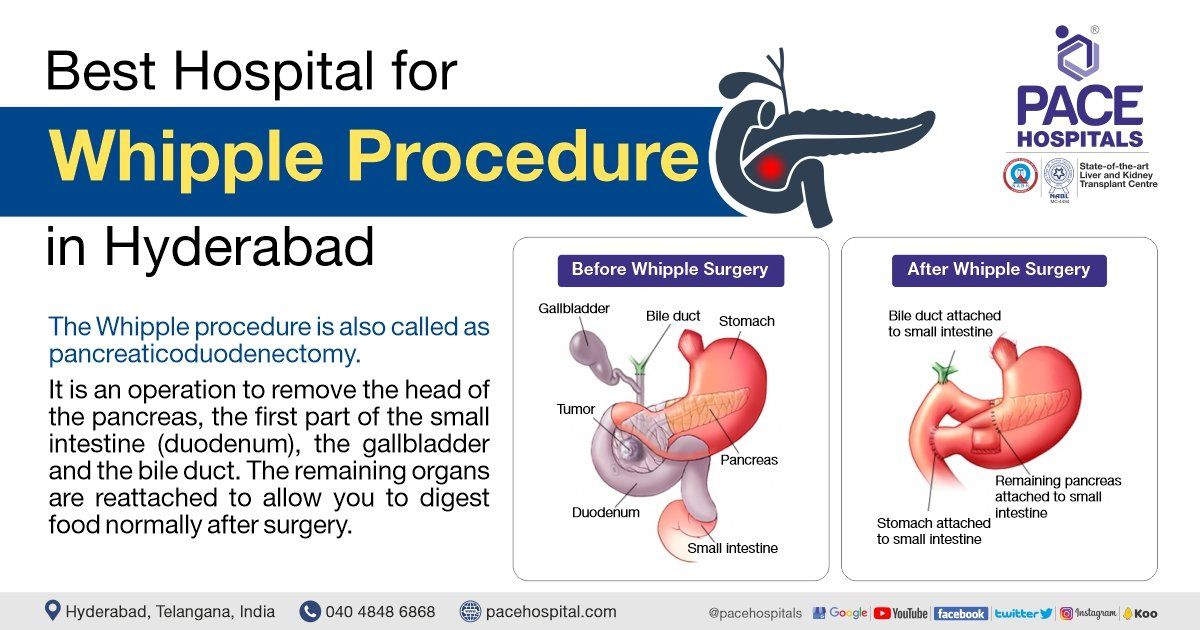

Pancreatic Cancer After Whipple Surgery

Pancreatic Cancer After Whipple Surgery

Whipple Procedure Steps Complications Purpose And More 40 OFF

https://lirp.cdn-website.com/69c0b277/dms3rep/multi/opt/Best+Hospital+for+Whipple+Procedure+in+Hyderabad-1920w.jpg